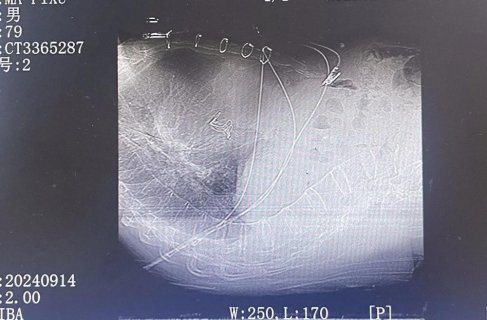

2025年6月14日14:00在家属的高度信任下,“战斗”正式开始。赵跃武主任医师带领团队按照预案有条不紊、稳步推进,虽术中惊险异常,但团队凭借经验均能娴熟应对。最终狭路相逢勇者胜,仅用时50分钟即在局麻下为老人完成主动脉瓣置换术(TAVR)。术后即刻彩超显示跨主动脉瓣的峰值压差由术前的85mmHg降至接近0、无瓣周漏,手术效果理想。